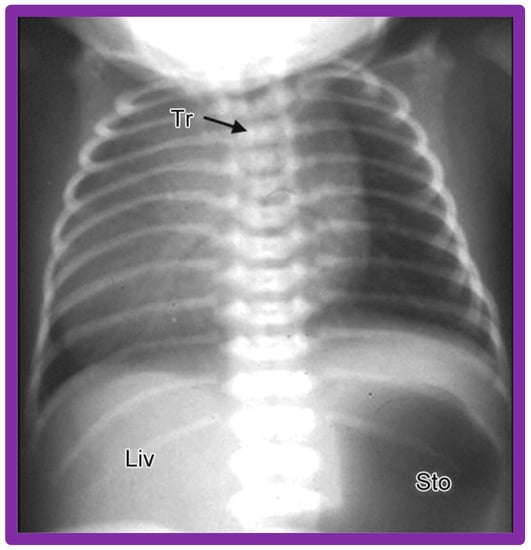

3.9. Isolated Dextrocardia

Isolated dextrocardia is a phrase used to characterize subjects with dextrocardia, but the viscera are normal in position (situs solitus), i.e., dextrocardia with situs solitus (Figure 3 and Figure 10).

Figure 10. A chest roentgenogram of a baby illustrating dextrocardia along with normal visceral position (situs solitus) with the liver (Liv) on the right side and the stomach (Sto) on the left side, i.e., isolated dextrocardia. The tracheal (Tr) position in the middle is shown. The Sto is dilated, probably related to intestinal obstruction secondary to malrotation of the gut. Modified from reference [4].